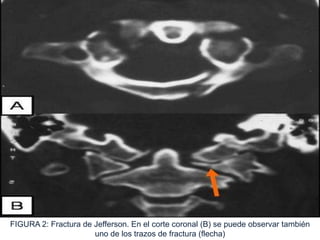

FIGURA 2: Fractura de Jefferson. En el corte coronal (B) se puede observar también

uno de los trazos de fractura (flecha)

 Fractura estallido o fractura de

Jefferson por compresión axial pura.

Representa el 2% de las fracturas

cervicales.

 40% asociado con fractura del axis (C-2).

 Por definición deben fracturarse

simultáneamente los arcos anterior y

posterior del atlas.

 En ocasiones, también se rompe el

ligamento transverso; esto hace que

los fragmentos se desplacen

lateralmente.